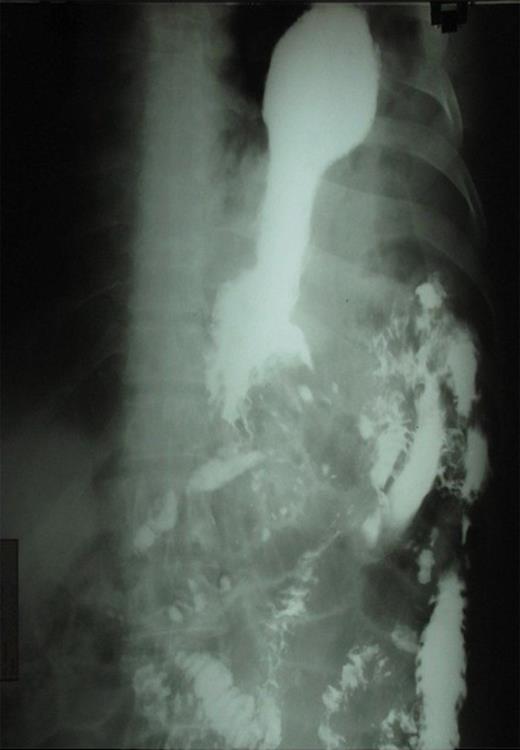

The presence of the nasogastric tube was confirmed with the presence of gurgling sound on auscultation after administration of air through it. Barium meal was carried out to localize the stomach and showed the presence of the stomach in the thoracic cavity confirming diagnosis of post-traumatic diaphragmatic hernia. (Figure 2)